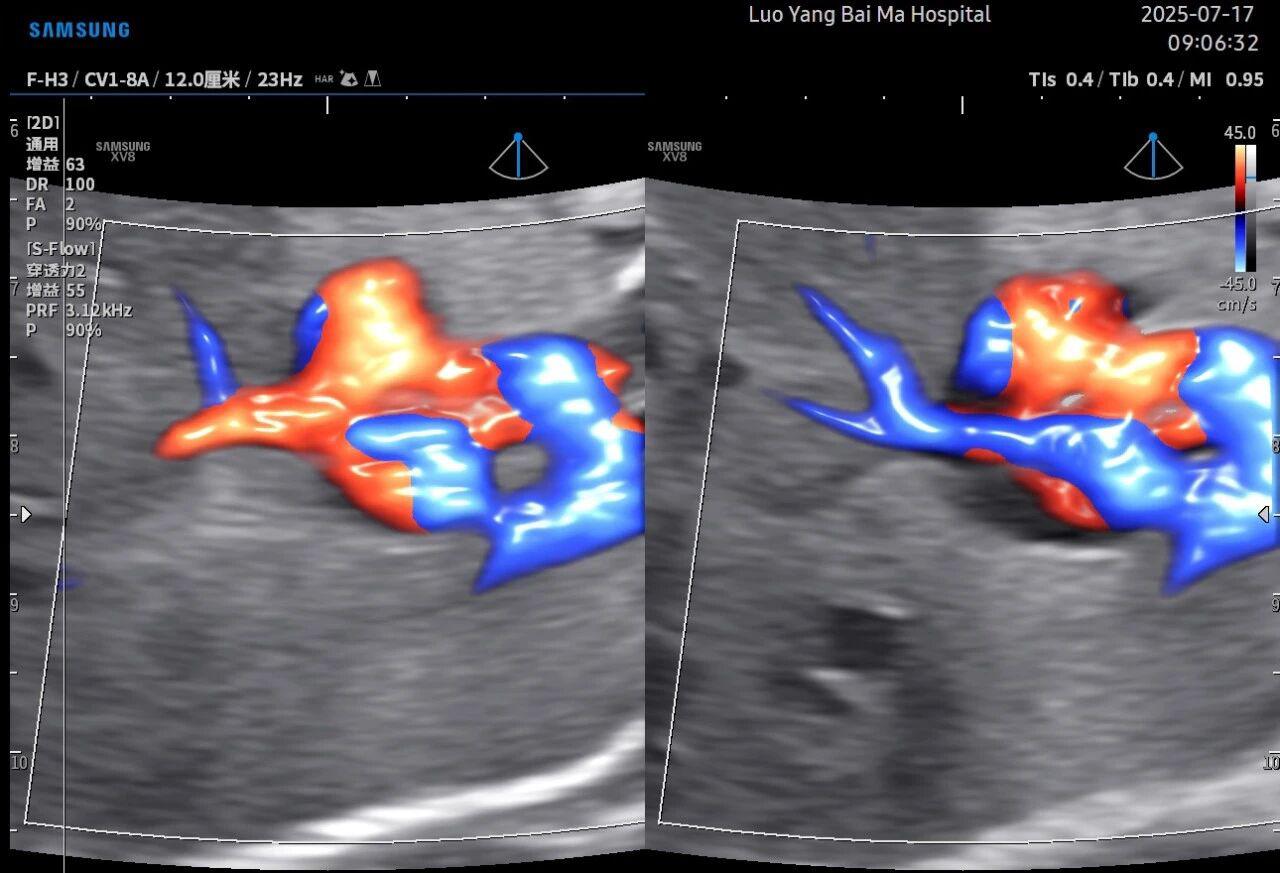

二、5D智能彩超在排畸检查中的独特优势

孕中期(通常在22-28周)的大排畸检查是整个孕期至关重要的环节之一。其目的在于系统地筛查胎儿是否存在结构性异常,如唇裂、脊柱裂、大脑、心脏、骨骼发育不良等问题。在这一关键检查中,5D智能彩超凭借其技术特性,展现出了显著的优势。

传统超声检查有时会因为胎儿体位、羊水量等因素的限制,导致某些部位观察不清。5D智能彩超技术能够实现对目标结构进行360°全方位、多切面的自由旋转观察。医生可以像“雕塑家”一样,从任意角度审视胎儿的解剖结构,尤其对于形态复杂的心脏、颅脑和脊柱等部位,这种能力可以极大弥补单一平面的局限性,帮助医生更全面地评估其发育状况。

这是5D技术的核心优势之一。系统内置了强大的智能化大数据分析功能和AI辅助诊断工具。例如,在进行胎儿颈项透明层(NT)测量、胎儿长骨(LB)测量等关键生物学指标评估时,5D智能系统可以自动识别解剖层面、智能勾勒测量范围并进行计算。这不仅大大缩短了检查时间,更重要的是,它通过标准化的智能算法减少了因人为操作可能产生的误差,使诊断结果更加客观、可靠。